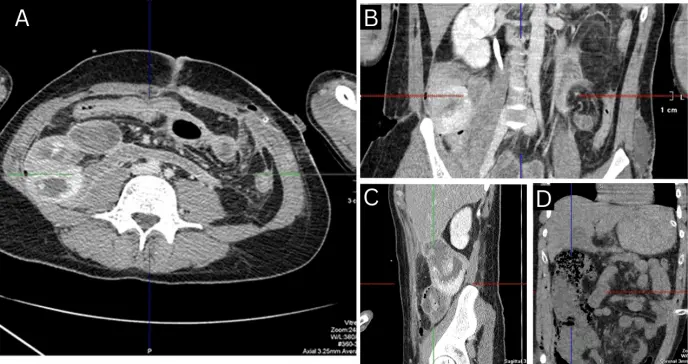

Se efectuaron suturas en las zonas lesionadas del tracto intestinal, empaquetamiento abdominal y formación de laparostomía. Cuatro horas después del evento, el paciente fue trasladado al hospital de Rol 4 del Ministerio de Defensa en Járkov, donde se completó su evaluación con exámenes de laboratorio y tomografía computarizada abdominal.

Los autores (Lurín) relatan que el día 25 se detectó una nueva perforación intestinal. En la cirugía se encontró una úlcera de 0,5 × 0,5 cm en el yeyuno, a 10 cm del ligamento de Treitz, con bordes regulares y sin sangrado activo. Se realizó su resección, cierre primario e intubación yeyunal. La laparostomía se mantuvo abierta debido al alto riesgo de recurrencia. La histopatología confirmó el diagnóstico de enfermedad de Crohn.